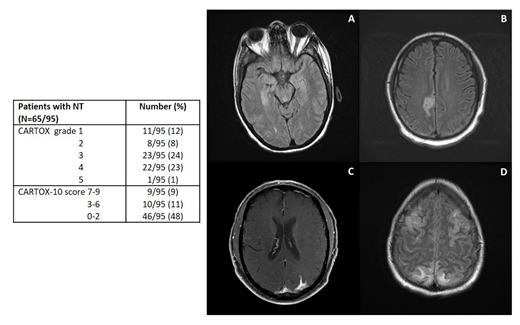

Results. Ninety-five pts were included in the study, 72 (76%) with diffuse LBCL, 17 (18%) with transformed follicular lymphoma, and 6 (6%) with primary mediastinal LBCL. Median age was 60 (range, 18-85), 71 (75%) were male. Median number of previous therapies was 4 (range, 2-15), 26 (27%) had a previous autologous stem cell transplant (SCT), and 1 (1%) a previous allogeneic SCT. Eight (8%) pts had prior central nervous system lymphomatous involvement (parenchymal in 5), and 39 (41%) had prior neurological and/or psychiatric medical history. After axi-cel infusion, NT of any grade was observed in 65 (68%) pts, grade ³3 in 46 (48%)(Table). No significant association was observed between above outlined baseline characteristics and development of NT. Median time from axi-cel infusion to NT onset was 5 days (range, 0-25 days) and median duration was 6 days (range, 1-52 days); no new onset/recurrent NT was observed beyond day 30.

Among the 65 pts who developed NT, a CT head without contrast was performed in 48, and was not evaluable in 2 because of motion artifacts. Among the 46 evaluable scans, 1 (4%) was abnormal as compared to baseline, and showed new onset cortical edema (non-diffuse but symmetrical). An MRI brain with contrast was performed in 36 pts, but was not evaluable in 10 because of lack of baseline, motion artifacts or differences in imaging sequences. Among the 26 evaluable scans, 15 (58%) showed abnormal findings, including autoimmune encephalitis-like, characterized by symmetric white matter changes of the pons and hippocampus (6; Fig. A), stroke-like (4; Fig. B), LMD-like (3; Fig. C) and PRES-like (2; Fig. D), with concomitant cortical edema in 5. EEGs were performed in 52 pts (>1/pt, for a total of 116 EEGs) and were abnormal in 47 (90%). Focal and/or diffuse slowing was the most common abnormality (isolated finding in 35 [73%] pts), while epileptiform discharges and/or non-convulsive status epilepticus (NCSE) were observed 12 (27%) pts. A lumbar puncture was performed in 12 pts: median white blood cell count was 2 cells/µL (range, 0-6), median protein 47 mg/dL (range, 13-600), median glucose 69 mg/dL (range, 30-111), and cytology was positive for malignant cells in 2 (7%) pts. Convulsive seizure was observed in 4 (6%) pts and 10 (15%) received additional anti-seizure therapy for convulsive or non-convulsive seizures. Among the 65 pts with NT, dexamethasone up to 20 mg IV Q6H was given to 42 (65%) pts, methylprednisolone 1000 mg IV daily to 12 (18%), and tocilizumab to 64 (98%; during CRS or CRS with concurrent NT).

Conclusions. Our results suggest that multiple radiological patterns of NT after axi-cel are possible in r/r LBCL pts, MRI being more sensitive than CT scan for their detection. NCSE is a common event, supporting the use of seizure prophylaxis and EEGs for evaluation of these pts. Pts with NT experience a worse outcome, and additional clinical and biological predictors of NT will be analyzed and presented at the meeting.